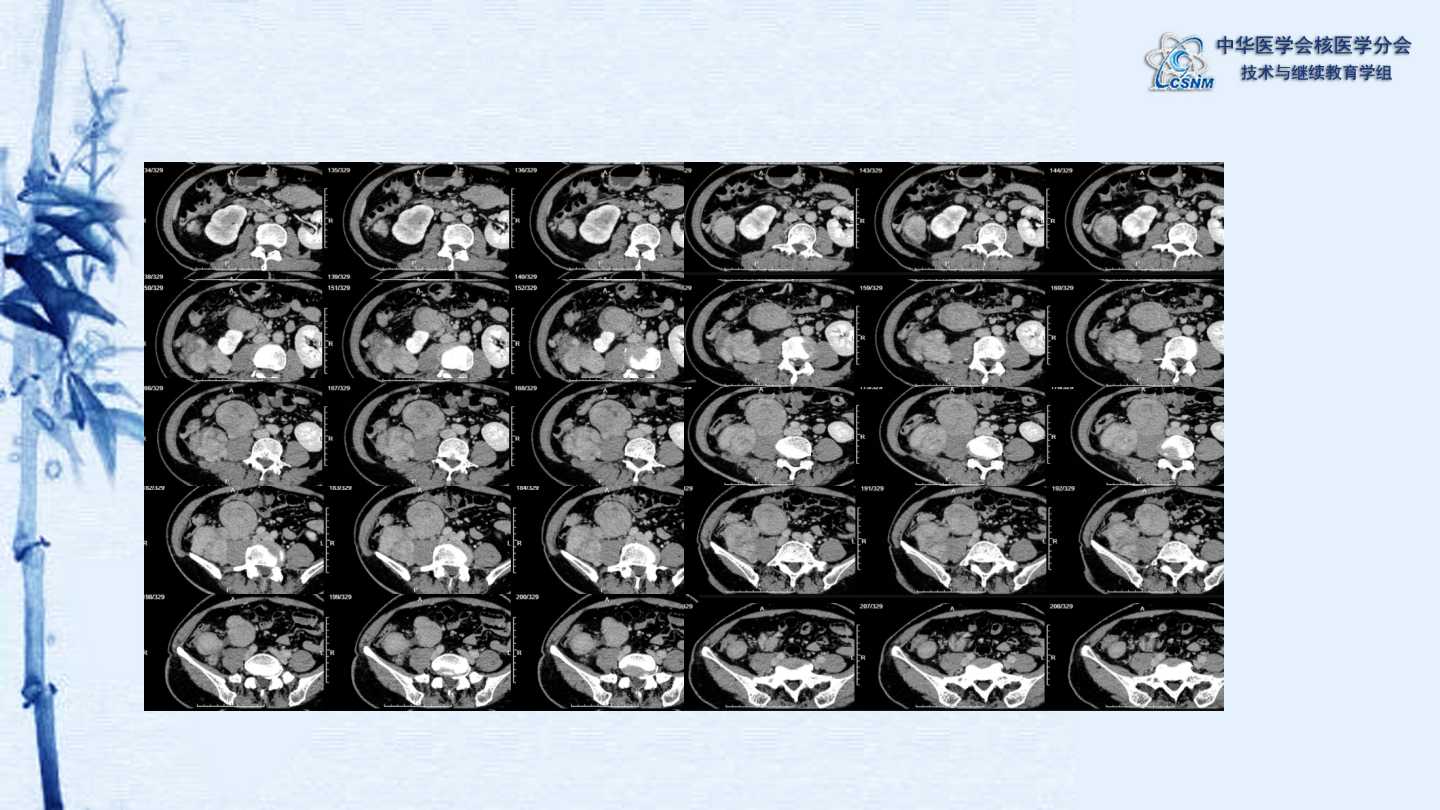

【CSNM继教学组】病例E51-邢岩-结肠炎性肌纤维母细胞瘤18F-FDG PET/CT显像